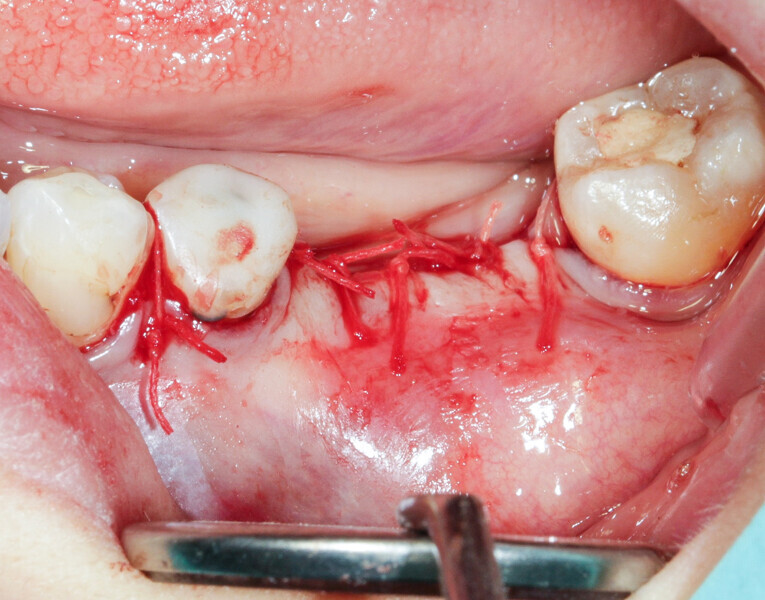

We had three alternative courses of action: a bone block graft from the mandibular ramus,2 a segmental osteotomy4 or a radicular graft, knowing that tooth #46 could not be saved. We chose the third option because it allowed for simultaneous implant placement and bone reconstruction. A large flap was elevated to assess the gap in the bone and in anticipation of closing the flap on an augmented ridge. Two implants were placed as normal despite the low residual bone thickness in the vestibular area of the planned positions for the implants (Fig. 5). The roots of tooth #46 were extracted atraumatically (root separation, use of piezo-surgery, etc.) and were then prepared as described. The roots were shaped to fit the defect and fixated at the insertion site using osteosynthesis screws (Fig. 6).3 The flap was mobilised and stretched to achieve edge-to-edge closure without tension, and a 4/0 rapidly resorbed braided thread was used for the sutures (Fig. 7). Four months after the bone augmentation and implant placement, healing abutments were connected to the implants and the osteosynthesis screws removed (Figs. 8 & 9). During the operation, time was taken to perform a visual check that ankylosis of the radicular grafts had been successful and that these were sound. Finally, a CBCT assessment was performed. The prosthesis was fitted by our colleague a few weeks later, once the soft tissue had healed.